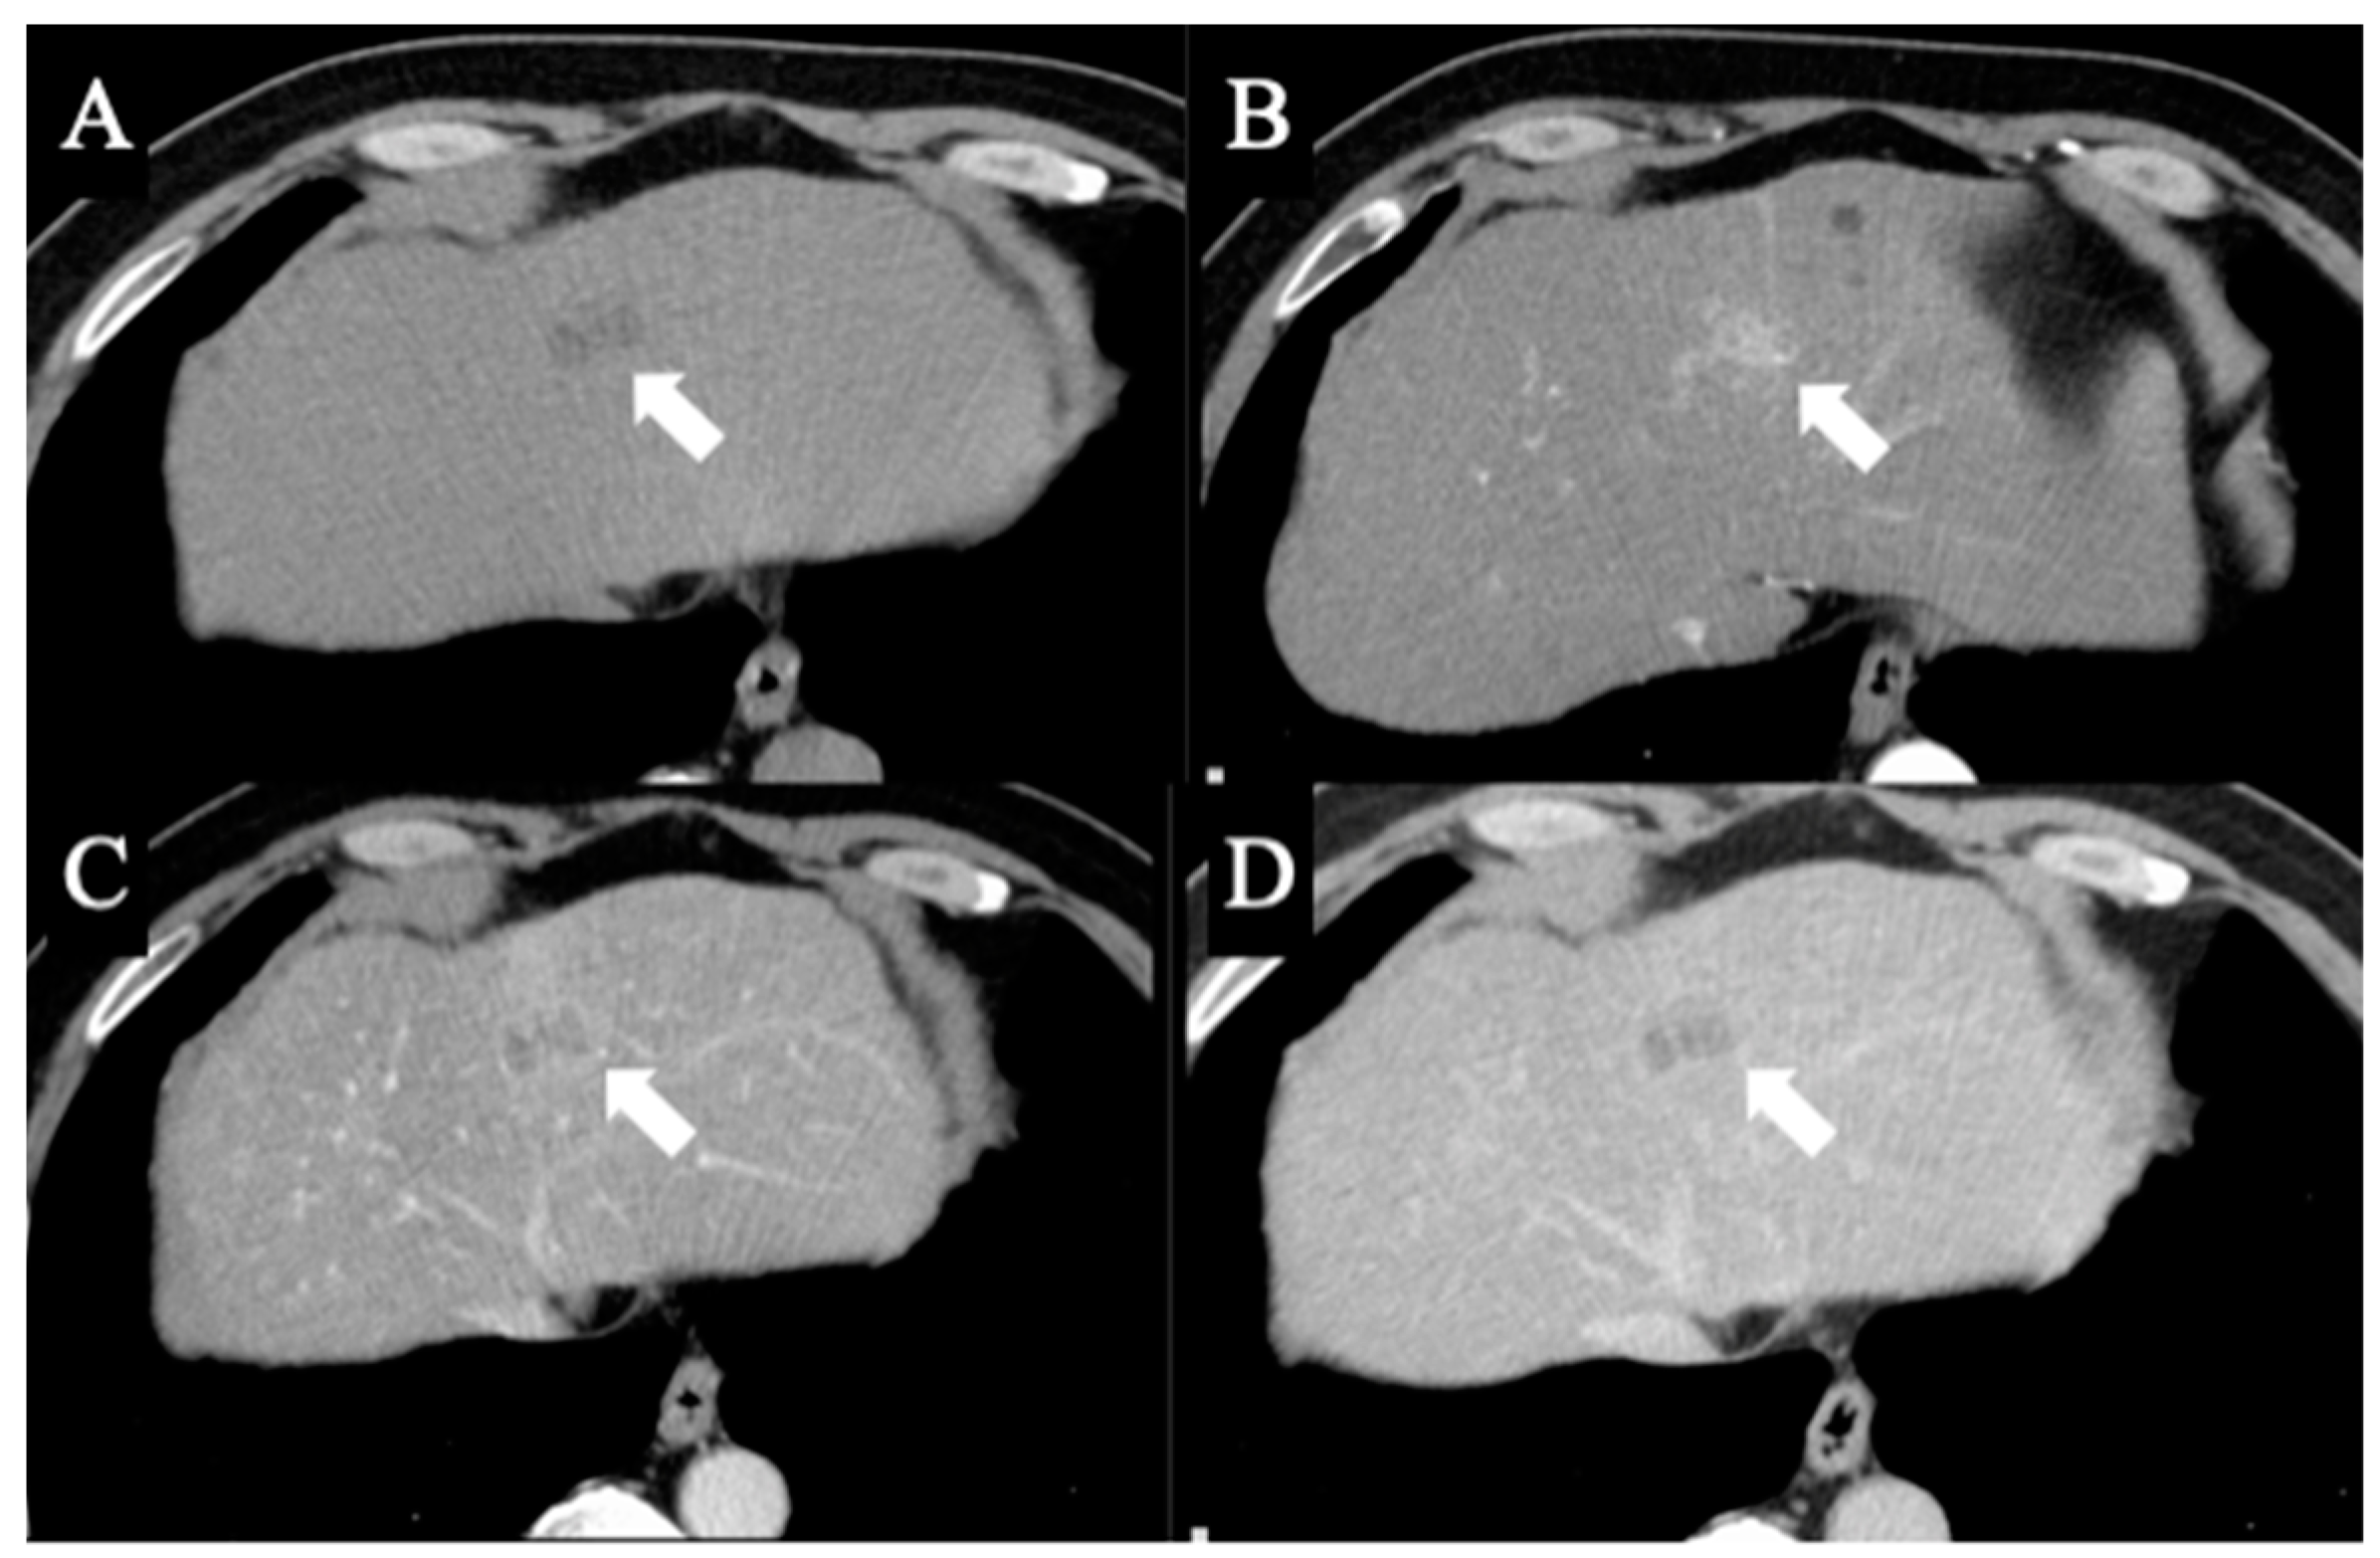

2. Case Report